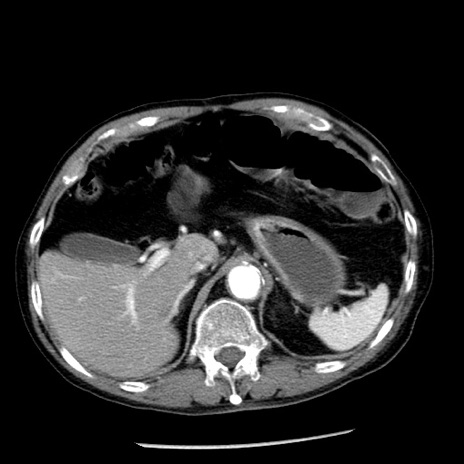

症例26(横断像)

【症例】80歳代男性

【主訴】嘔吐

【現病歴】昨晩2回嘔吐あり、今朝になっても嘔吐あり。来院。

【既往歴】胃潰瘍

【身体所見】意識清明、BT 37.6℃、BP 166/95mmHg、HR 100bpm、SpO2 97%、腹部:平坦・軟、腸蠕動音聴取良好、圧痛なし。

【データ】WBC 21900、CRP 1.46